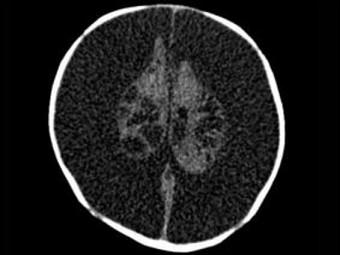

问题 3个月男婴,头颅迅速增大,发育停滞,CT表现如图,可能的诊断为 ( )

选项 A、先天性脑积水 B、重度脑积水 C、慢性双侧性巨大硬膜下血肿 D、水瘤 E、脑严重缺血

答案 A